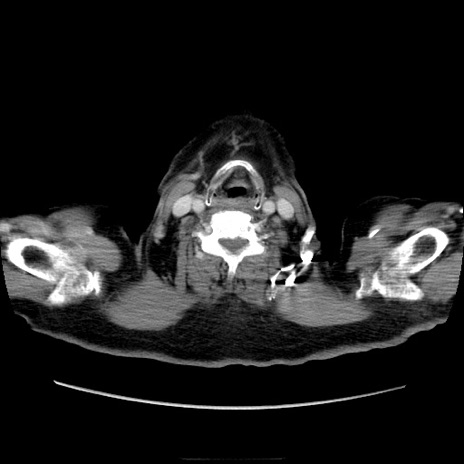

冠状断像

【症例】70歳代男性

【主訴】腹痛

【現病歴】肝硬変・肝細胞癌にてかかりつけの方。約9時間前に食後より腹痛出現。症状が徐々に増悪し、嘔吐出現したため来院。

【既往歴】肝硬変、肝細胞癌(RFA、TACE後)

【身体所見】意識清明、表情苦悶様、BT 36℃、BP 129/78mmHg、P 88bpm、SpO2 97%(RA)、右上腹部から心窩部にかけて圧痛あり、反跳痛なし、筋性防御あり。

【データ】WBC 5800、CRP 0.16